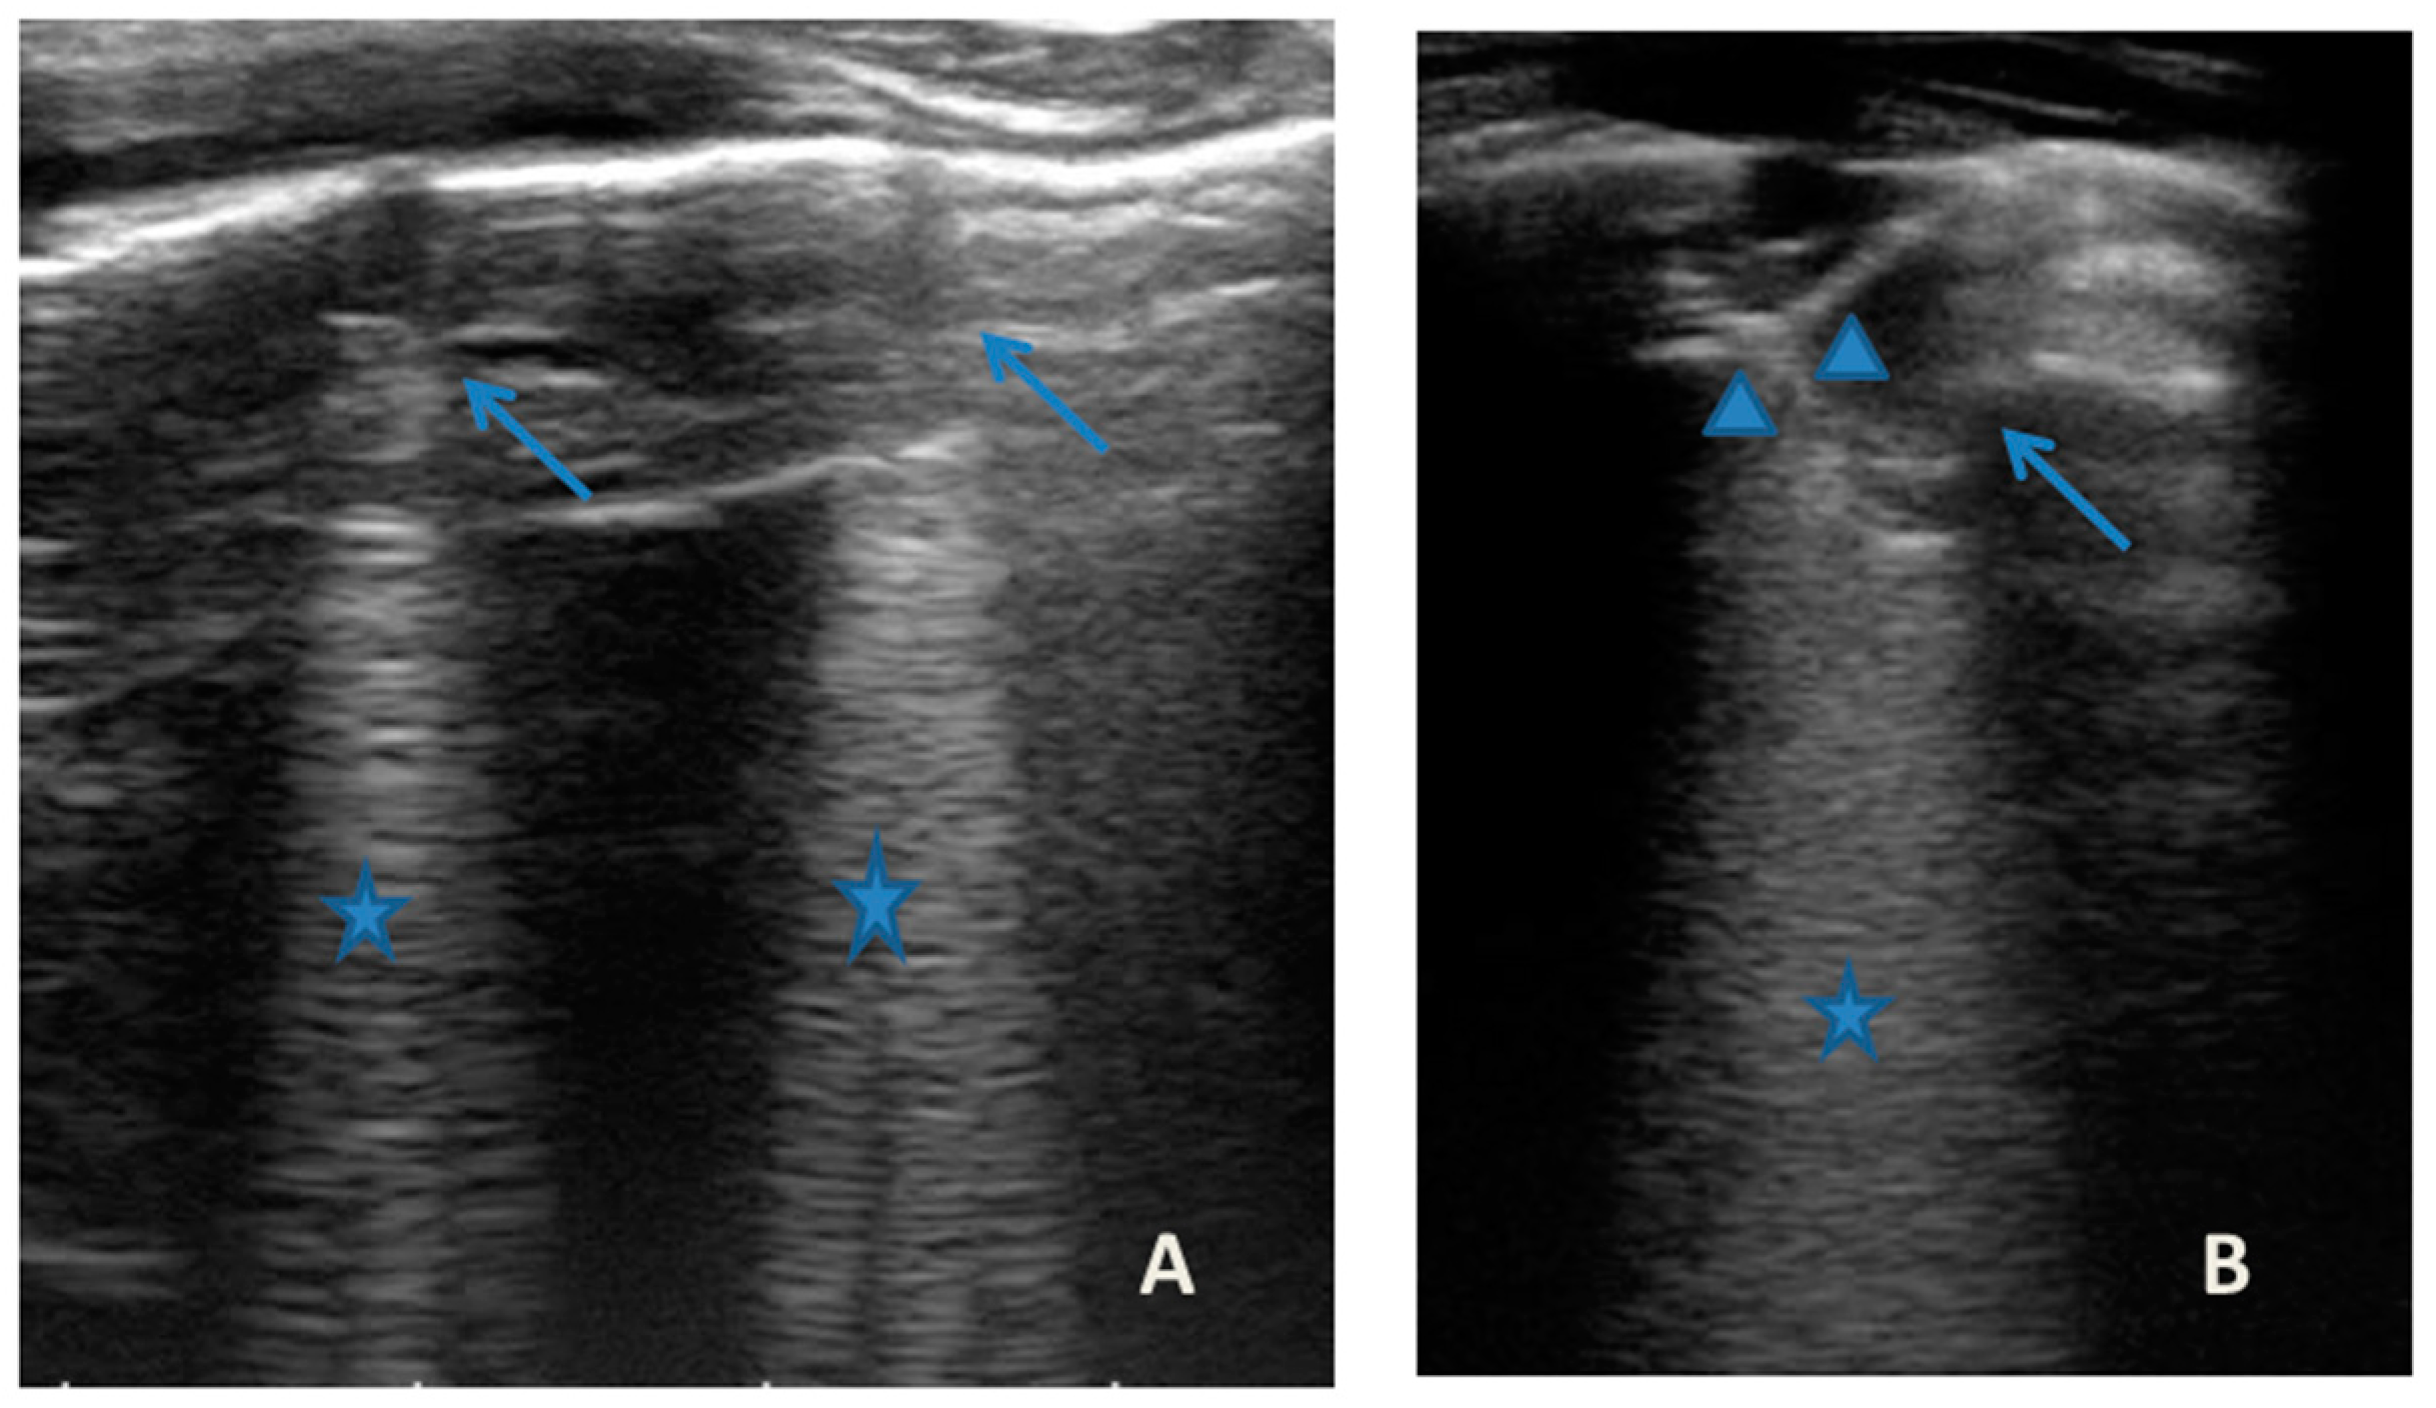

She came to our attention at the PED for acute onset of asthmatic bronchitis, with mild respiratory distress, fever, and rhinitis present for three days. She was mildly dyspneic, in good general condition, and with stable vital signs. She did not need oxygen. Upon examination of the chest, she presented with diffuse bronchospasm, associated with rales spread throughout the lung area. She had a moderate rise in the inflammation indices. At the same time as the first clinical evaluation, we performed LUS, which showed a picture compatible with acute inflammation of the small airways (Figure 7). This picture was also confirmed by the microbiological data of positivity of the nasopharyngeal swab for RSV. Respiratory symptoms resolved after 72 acute phase therapy. The patient was discharged with the preventive therapy already in progress. LUS follow-up showed the complete resolution of the ultrasound picture after a total of 5 days.

Figure 7.

Grayscale lung ultrasound examination shows: (A): sub-centimeter consolidations less than 0.5 cm in size (arrows), associated with confluent artifacts (asterisks) in the left lateral mid-apical area; (B): a small consolidation of 0.5–1 cm (arrows), with elements of dynamic air bronchogram (arrowhead) (as per suspected inflammation) [10,14,15], associated with a circumscribed area of “white lung” (asterisks) in the right middle apical area; (A,B): irregularity of the pleural line. Picture compatible with acute inflammation of the small airways of viral origin [14,15].

In our cases (Table 1), particularly in the first three cases—children with asthma not controlled due to an inadequate preventive therapy for age, phenotype, and severity of the clinical picture [1,2]—LUS was highly positive (Figure 1, Figure 3 and Figure 5). It showed the presence of lung atelectasis, which resolved slowly after weeks of therapy of the acute attack and the beginning of adequate preventive therapy. On the contrary, in case 4 and 5—children with asthma well controlled by adequate preventive therapy—LUS was not highly positive (Figure 6 and Figure 7). In fact, it did not show large atelectasis, but a slight SIS in case 4, and a SIS suggestive of viral infection of the small airways in case 5 [14,15].